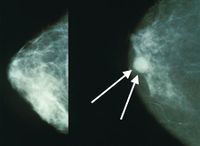

سرطان الثدي

| سرطان الثدي | ||

| معدل الانتشار | 2.1 مليون (2015) | |

| معدل البقاء 5 سنوات | ~85% (الولايات المتحدة والمملكة المتحدة)[4] [5] | |

| حالات الوفاة | 533.600 (2015)[6] | |

| عوامل الخطورة | طفرات موروثة في الجين BRCA1 أو الجين BRCA2؛ تقدم العمر؛ البدء المبكر للحيض؛ تأخر الإياس (سن اليأس)، عدم إنجاب أي طفل أو إنجاب الطفل الأول بعد سن الثلاثين؛ التاريخ الشخصي personal history أو العائلي للإصابة بسرطان الثدي؛ وربما يكون للغذاء الغني بالدهون دور في ذلك. تنخفض معدلات الوفيات بين النساء البيض ولا سيما اللواتي تقل أعمارهن عن الخامسة والستين. | |

| العلامات المنذرة | وجود كتلة غير مؤلمة في الثدي هو علامة نموذجية، وقد تكون مؤلمة أحيانا؛ أي تغير في لون أو شكل أو طبيعة نسيج الثدي أو الحلمة؛ إفراز discharge من الحلمة أو التألم عند جَسِّها. | |

| الكشف والتشخيص | الفحص الذاتي والفحوص السريرية للثدي، تصوير الثدي الشعاعي mammogram. ينصح الخبراء أن يُجرى سنويا تصوير شعاعي وفحص عام للثدي لجميع النساء اللواتي تتجاوز أعمارهن الخمسين، بل ولبعض النساء الأصغر أيضاً.

| |

| العلاج | يمكن أن يكون الاستئصال الكامل للثدي mastectomy مناسبا للأورام الموضّعة. وقد يفضل في كثير من الأحيان الجراحة المحافظة على الثدي breast-conserving surgery (بإزالة الورم وبعض النسج المحيطة به وتسمى أحياناً استئصال الكتلة lumpectomy) متبوعة بمعالجة شعاعية موضعية. وعلى الرغم من أن نسبة المعاودة (الانتكاس) أكبر في الجراحة المحافظة على الثدي، فإن هذه المعاودات يمكن علاجها باستئصال الثدي كاملا. وعلى كل حال، فإن نسبة البُقيا في هذه الحالة مساوية للحالات التي تعالج باستئصال الثدي في البداية. وقد يُتبع كل من الإجراءين بمعالجة كيميائية إضافية أو بمعالجة حاصرة للهرمونات. وإذا كانت الخلايا الورمية تحوي مستويات عالية من مستقبلات هرمونات الإستروجين والپروجسترون فإن هذا مؤشر جيد، إذ تستطيع المعالجة الحاصرة للهرمونات إيقاف نمو هذه الخلايا.

| ملاحظات | آراء خلافية: على الرغم من أن الفحوص التي تُجرى للكشف عن الطفرات الوراثية في الجينيْن BRCA1 و BRCA2 قد صارت متوافرة، فإن الأطباء لم يصلوا إلى إجماع على استخدام هذه الفحوص. كما أن جدوى إجراء المعالجة الكيميائية عند المريضات المسنّات وجدوى تصوير الثدي الشعاعي الروتيني لمن لم يَبْلغن سن الخمسين، ما زالتا موضع جدل. وتشير بعض الدراسات إلى أن المعالجة الجراحية لسرطان الثدي خلال النصف الثاني من الدورة الطمثية للمريضة قد تعطي نتائج أفضل. | |